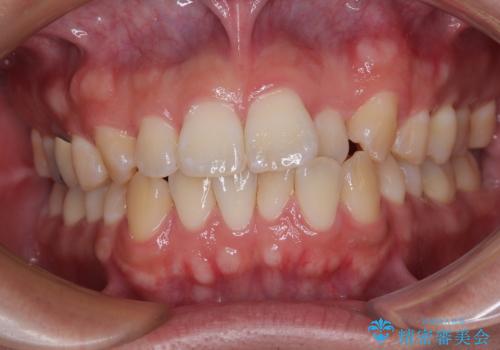

- 飛び出した前歯と全体的なデコボコを気にして来院された患者様です。

ワイヤーでもマウスピースでも治療可能でしたが、自己管理の重要なマウスピース矯正は自分には向かないとのことで、ワイヤー矯正で治療することとしました。

大きなトラブルもなく、順調に歯列が整ったため、僅か9ヶ月で装置を外すことができました。

あまりに短期間であったため、患者様自身も非常に驚いていらっしゃいました。